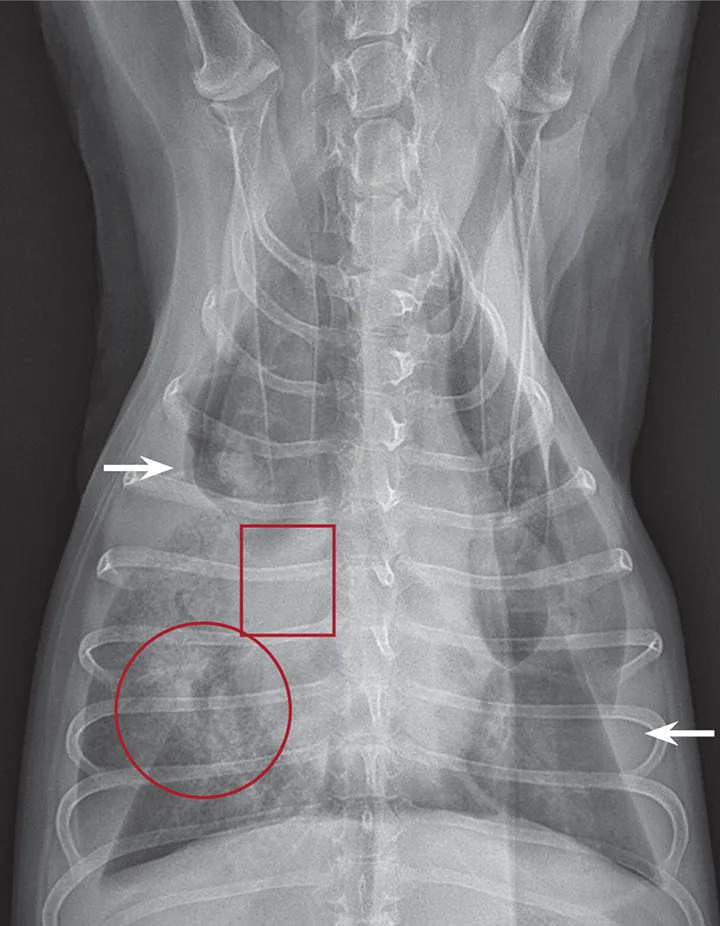

Figure 2

Ventrodorsal thoracic radiograph of a dog with right middle LLT. There is a vesicular gas pattern and alveolar pattern throughout the right middle lung lobe (circle), and the right middle lobar bronchus abruptly truncates near the hilus (rectangle). There is a moderate volume of pleural effusion evenly distributed within the pleural space, with moderate retraction of all lung lobes away from the thoracic wall (arrows).